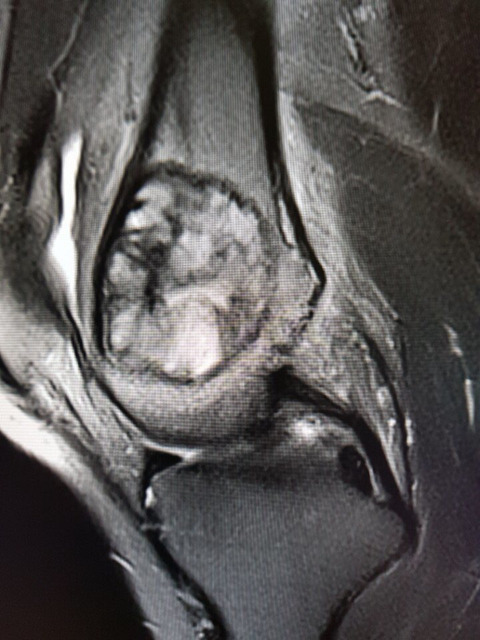

무릎 거대세포종

6월부터 통증있다가 8월말 mri 찍고 삼성의료원 방문하여 조직검사 후에 9.13 거대세포종 판정 받았습니다.

수술은 10.5 예정이고, 교수님께서 골 소파술 이후 골시멘트로 채울 계획이고, 관절은 안건드린다고 하셨습니다.

크기는 지름 3.5cm

• 작성자소중한분 작성자 본인 여부 작성자 | 작성시간 18.10.09 댓글 첨부 이미지 이미지 확대